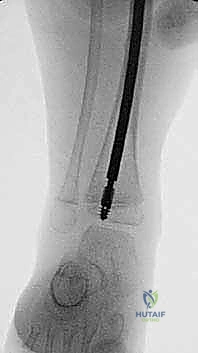

الدليل التفصيلي لخطوات العملية الجراحية: بضع العظم عبر الجلد والمسامير التلسكوبية

تُعد هذه العملية من أدق العمليات في جراحة عظام الأطفال، وتتطلب مهارة استثنائية كما هو الحال مع البروفيسور محمد هطيف. يتكون المسمار التلسكوبي (Fassier-Duval) من جزأين يتداخلان ببعضهما البعض (مثل التلسكوب). يتم تثبيت أحد الأطراف في أعلى العظم والطرف الآخر في أسفله. عندما ينمو العظم، ينزلق الجزء الداخلي من المسمار للخارج، مما يسمح للعظم بالنمو الطبيعي دون أن ينثني أو ينكسر.

الخطوة الرابعة: إدخال المسمار التلسكوبي

بعد تقويم العظم وجعله مستقيماً كحبات المسبحة على خيط، يتم إدخال السلك الدليلي (Guide Wire). ثم يتم إدخال الجزء الخارجي (الأنثوي) من المسمار التلسكوبي وتثبيته في الجزء العلوي من العظم (Epiphysis).

بعد ذلك، يتم إدخال الجزء الداخلي (الذكري) من المسمار عبر الجزء السفلي من العظم وتثبيته في المشاشة السفلية. هذا التصميم العبقري يضمن حماية العظم بالكامل من الداخل.